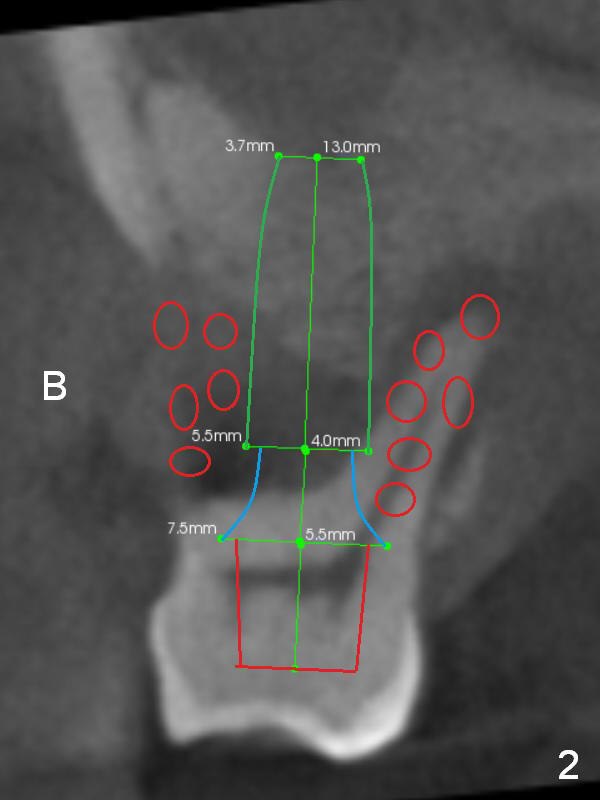

It may take 6 months for #19 implant re-placement after socket preservation. The tooth #3 is symptomatic (Fig.1). In spite of implant failure at #19, the best treatment for #3 of the same patient is still immediate implant. Previous practice is to place an implant as long as possible (Fig.2). The coronal threads are not covered by the native bone. Bone graft (red circles) cannot guarantee thread coverage. Periimplantitis may develop more likely in periodontitis patients if bone graft is not tightly packed.

When the crown at #19 is cemented, the tooth #3 is found to have severe buccal recession (Fig.4). A 5.3x10 mm implant is not only placed deep, but also palatal (Fig.5, Clindamycin). An abutment will be selected with the longest cuff (6 mm (pink)). To make the palatal gingival margin recede, the coronal palatal bone (<) will be broken and pushed to the palatal socket.